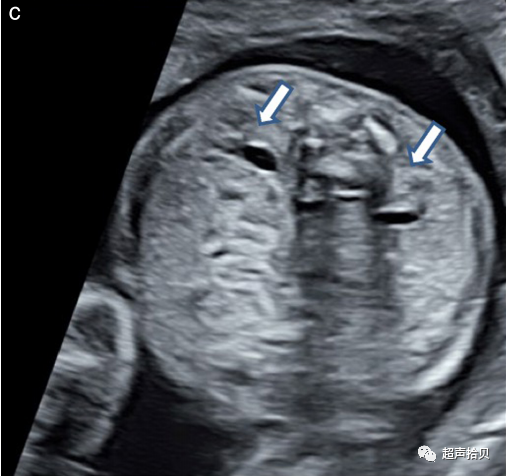

图2胎儿头部的横切面,显示标准的经脑室(a)、经小脑(b)和经丘脑(c)扫描平面。经脑室和经丘脑平面允许评估大脑半球区域的解剖完整性。经小脑平面允许评估后颅窝的小脑和大池(CM)。CP-脉络膜丛、CSP-透明隔腔、TH-丘脑。

大脑

用于胎儿大脑基本检查的标准扫描平面在更新的 ISUOG 指南20中有描述。两个横断面,通常称为经脑室平面和经丘脑平面,可以显示与大脑解剖完整性相关的大脑结构(图 2)。成像伪影掩盖了近端半球(更靠近探头的半球)。应添加第三个横断面-经小脑平面来评估后颅窝。应评估以下大脑结构: